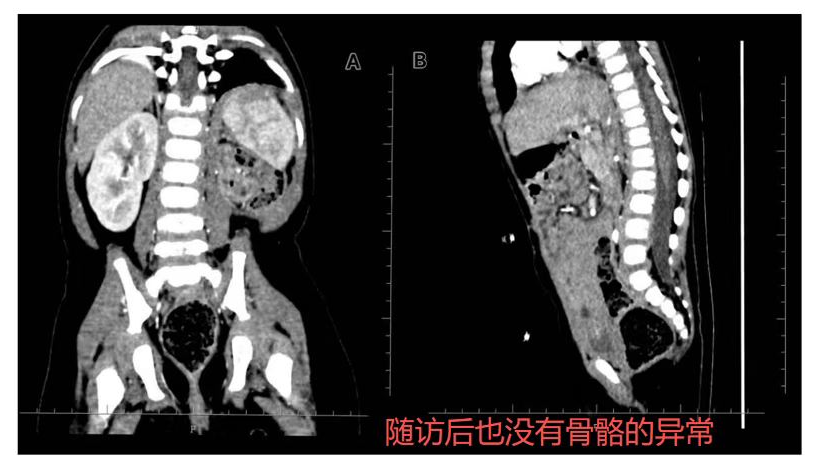

「此外,团队在治疗过程中针对脊柱及生长板的精准照射做了充分优化。通过剂量学优化设计,显著降低了脊柱和生长板的辐射剂量,确保了在治疗后 1 年的随访中,患儿未见明显的脊柱侧弯或生长抑制。」

值得高兴的是,经过 1 年的随访,患儿无肿瘤复发,肾功能和肝功能持续保持在正常范围,进一步验证了质子治疗的长期安全性与疗效。这一结果不仅证明了治疗的有效性,也为质子治疗在高风险婴幼儿群体中的应用提供了更强的支持。